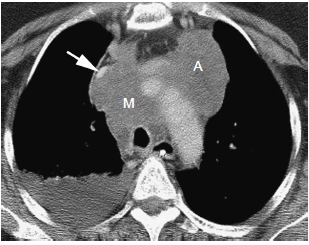

小细胞肺癌:交互式ct案例研究

小细胞肺癌CT